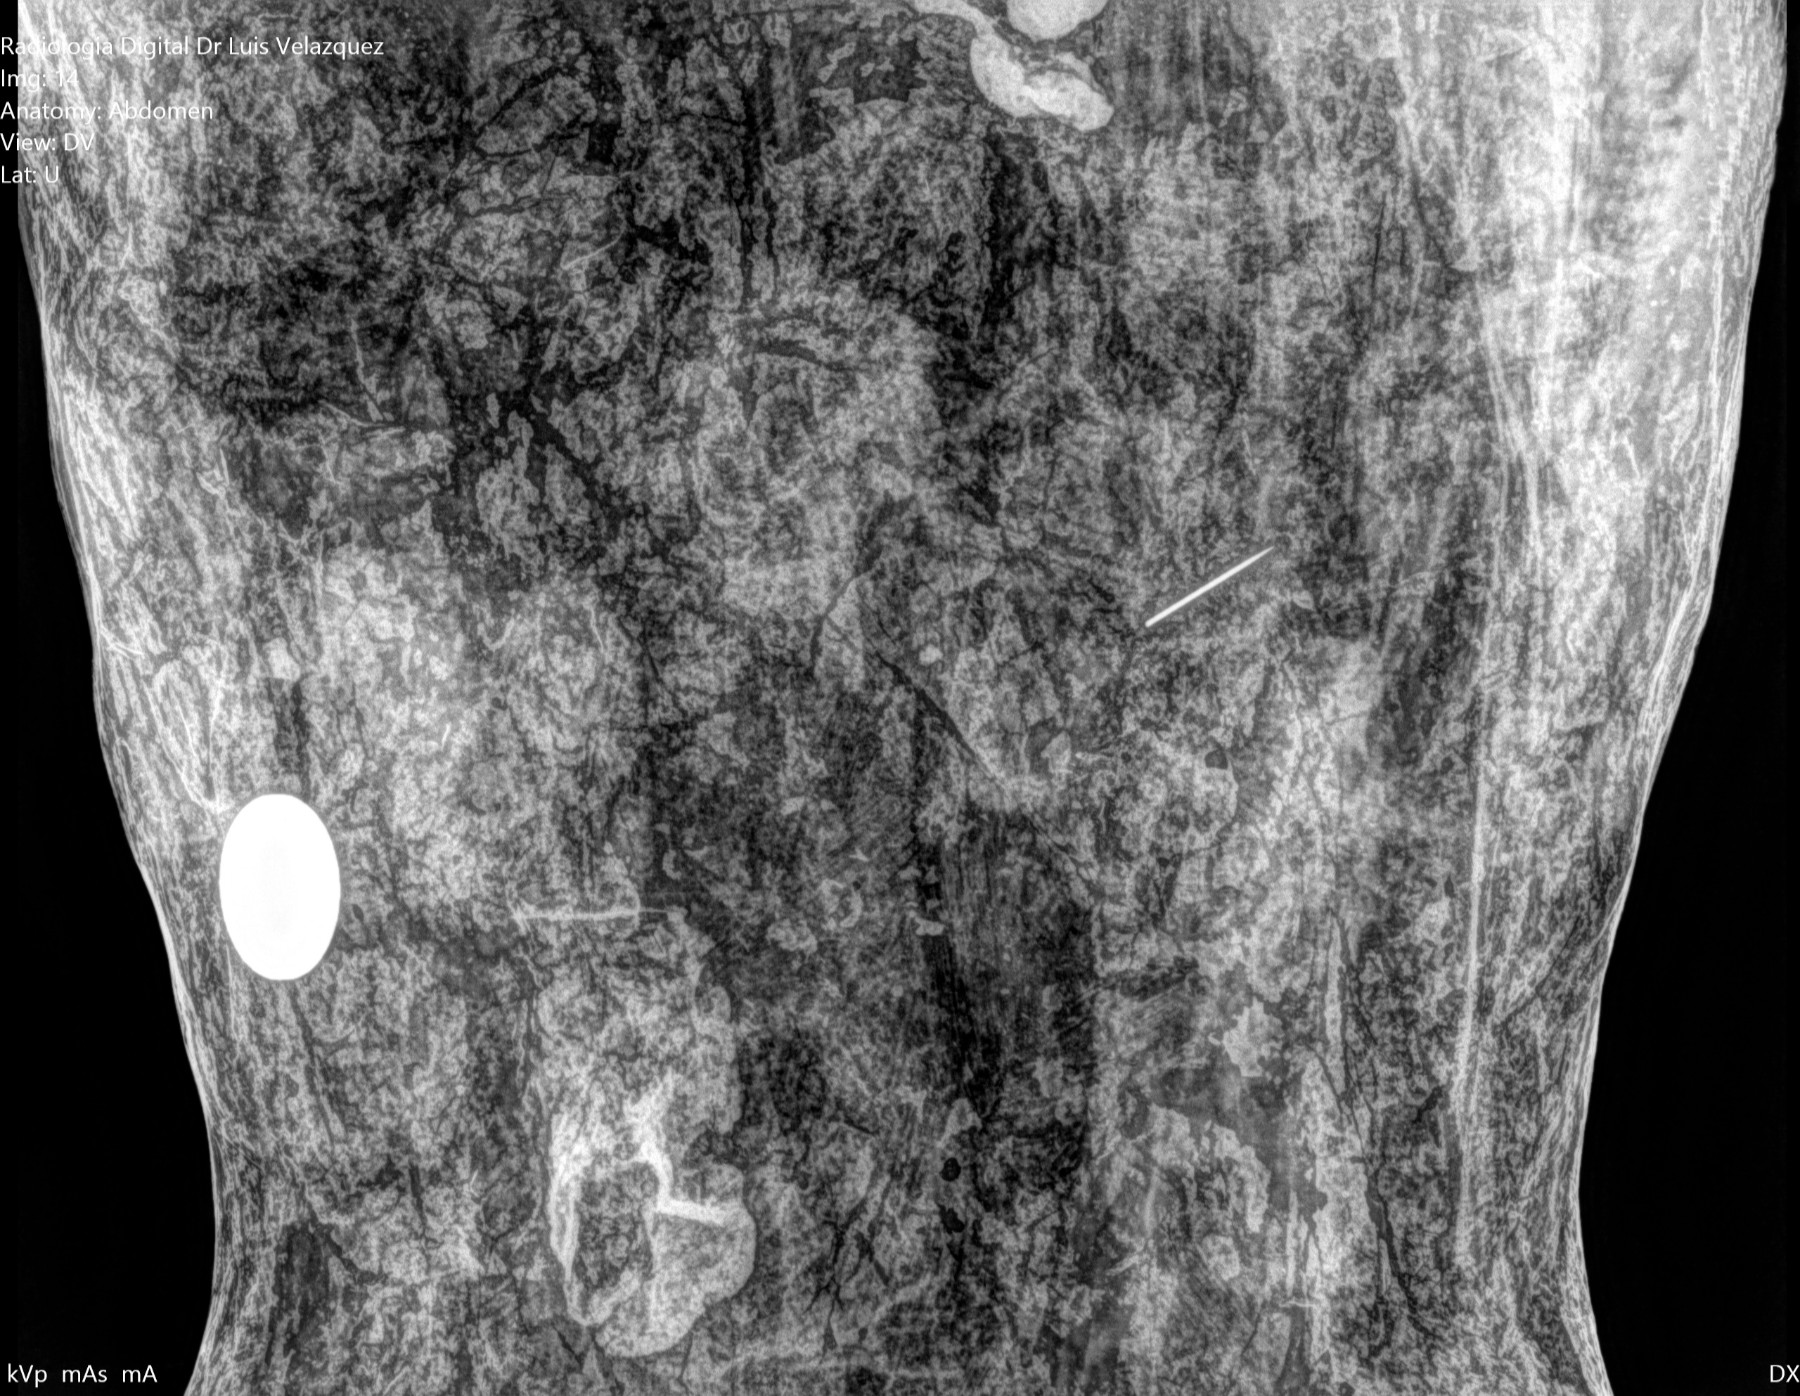

Desde el descubrimiento de los rayos “X” y las placas radiográficas por Wilhelm Conrad Roentgen y su posterior difusión a través de la Asociación Físico médica de Wurzburg el 28 de diciembre de 1895, que fue la primera asociación que habló de los nuevos rayos que podían penetrar el cuerpo y fotografiar los huesos, ha habido muchos cambios tanto en la forma de obtener, procesar e incluso en la forma de visualizar, manejar y almacenar las placas radiográficas.